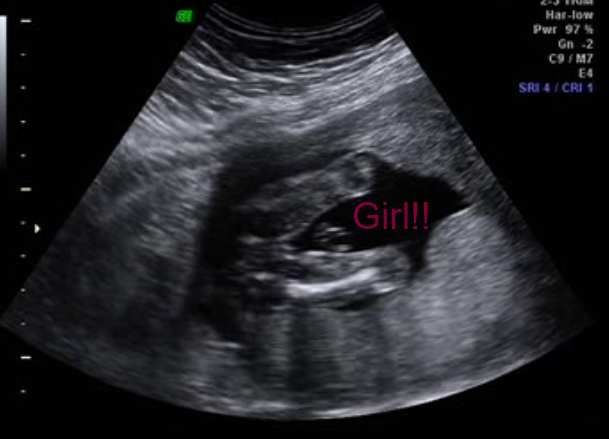

I have a picture here captured from the video, it's not the clearest pict in the world, so I will post a link to the video of my ultrasound as well.

I know what I think the baby is but I am so interested to hear what all of your guesses are.